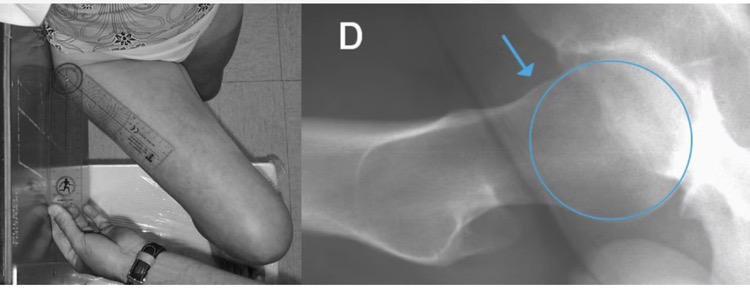

- 1. Le conflit de type CAM (a): excès d'os de la tête et le col fémoral => pas parfaitement ronds